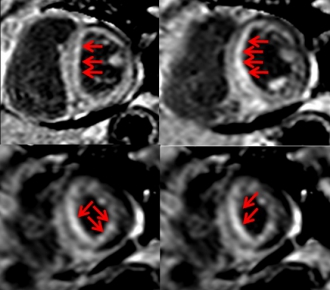

心アミロイドーシスの症例。心内膜側全体に遅延造影を認める(矢印)。